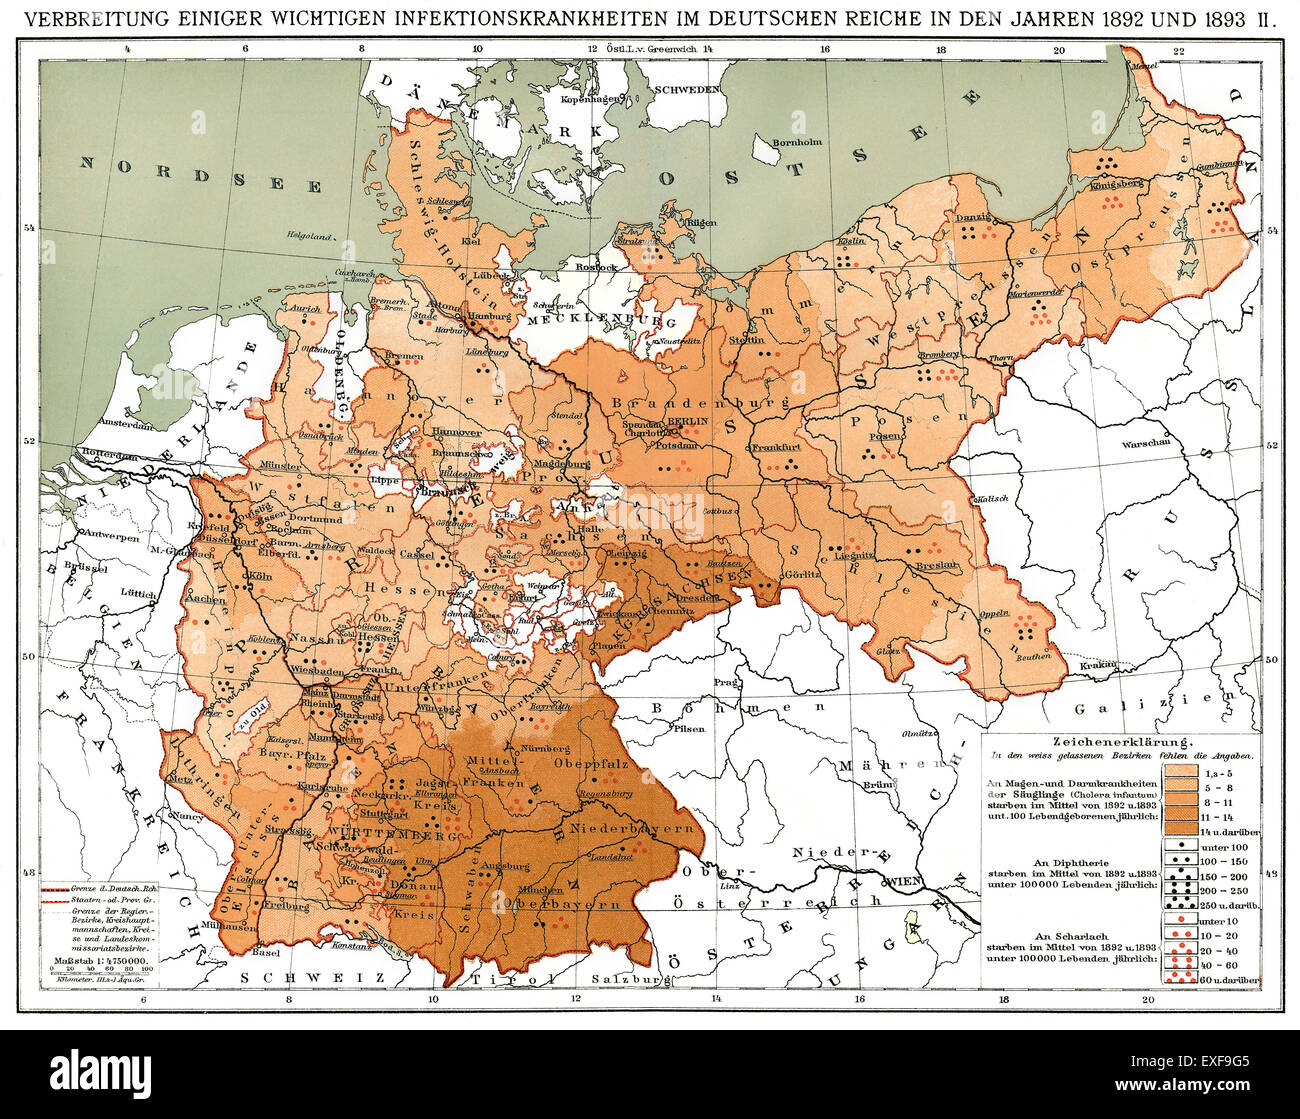

RMEXF9G5–Carte historique, propagation des maladies infectieuses dans l'Empire allemand en 1892 et 1893

RMEXF9AD–Carte historique, propagation des maladies infectieuses dans l'Empire allemand en 1892 et 1893,